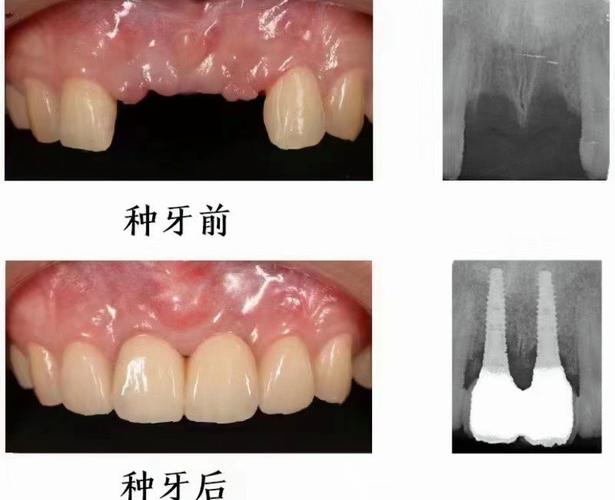

- 种植牙的原理是将人工牙根(种植体)植入牙槽骨内,等待其与骨头牢固结合(骨结合)。

(图片来源网络,侵删)在某些颌骨囊肿或肿瘤手术中,为了最大限度保存骨量和功能,医生可能会考虑在手术同期植入种植体(即刻种植),但这同样需要评估剩余骨量和未来发育潜力,风险较高,需要非常谨慎。